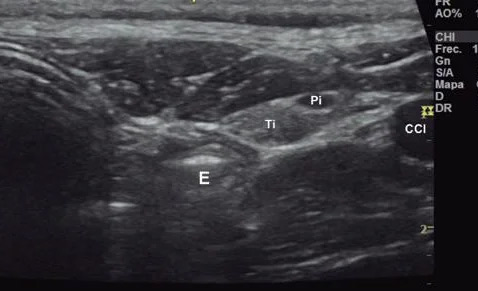

Tiroides

Es un estudio para obtener imágenes de la glándula tiroides que es una glándula ubicada en el cuello que regula el metabolismo (todos los procesos que controlan el ritmo de actividad de las células y los tejidos). Es un procedimiento indoloro y sin riesgo que se utiliza para evaluar el tamaño, estructura y presencia de nódulos y quistes.